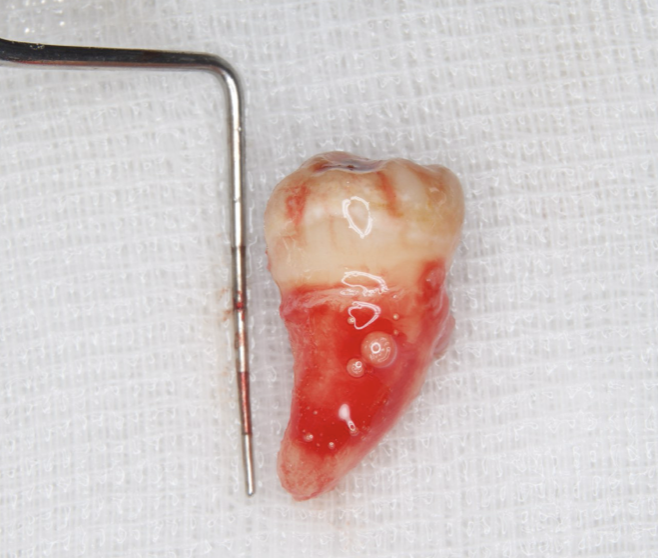

The patient was given amoxicillin/clavulanic acid at 250 mg (Sawacillin Capsules, Japanese Pharmacopoeia, Japan) one hour prior to surgery. Under local anesthesia (GINGICAINE GEL, Hakusui Trading CO., LTD, Tokyo, Japan ), with an inferior alveolar nerve block used for tooth #46 alonb with 2% lidocaine and 1:80000 epinephrine (Dentsply, Tokyo, Japan), that tooth was separated and its fragments were gently extracted with a dental elevator. Granulation tissue was then removed and the socket was prepared with an internal cooling carbide bur. The graft bed was formed using the CT measurements as an index. Abundant rinsing with 0.05% chlorhexidine gluconate and sterile saline (OTSUKA NORMAL SALINE, Otsuka Pharmaceutical Factory, Inc., Tokushima, Japan) was performed to eliminate debris. Tooth #48 was gently extracted with forceps and dental elevators, and meticulously examined, and the absence of fractures was confirmed. Also, the periodontal ligament in the extracted graft tooth was observed and considered to be sufficient, then, after measuring length with a probe, it was stored in saline (Figure 4).

Figure 4.Extraction of #48 was performed without damaging the periodontal ligament. Abundant periodontal ligament tissue could be seen.